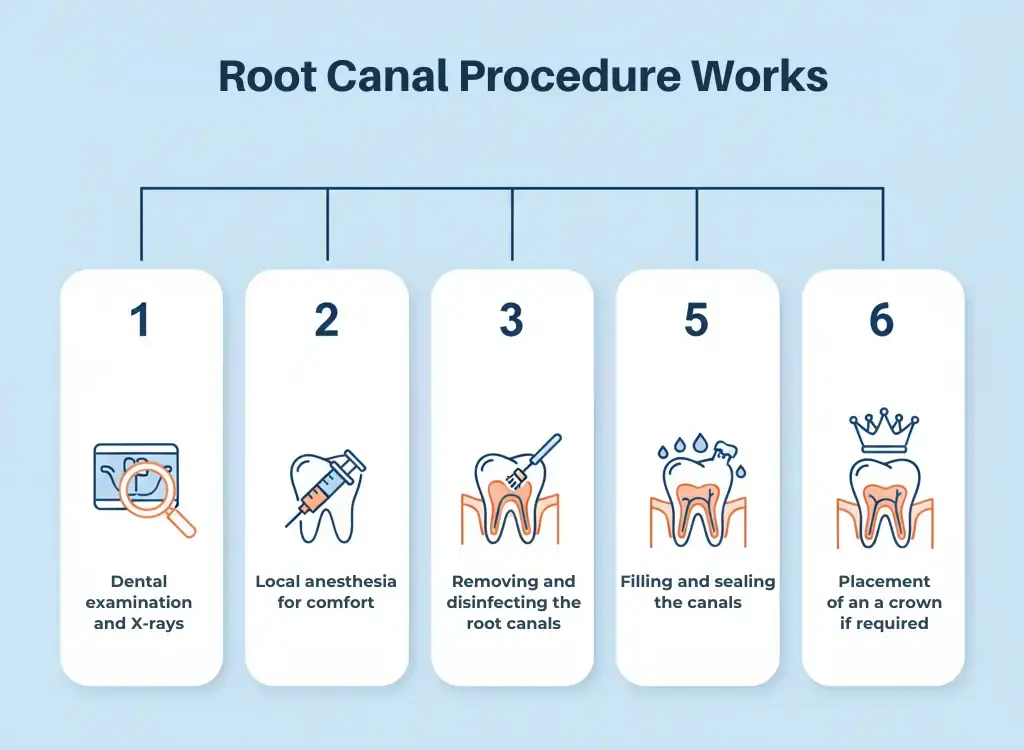

How the Root Canal Procedure Works

The treatment usually involves:

Dental examination and X-rays

Local anesthesia for comfort

Removal of infected pulp

Cleaning and disinfecting the root canals

Filling and sealing the canals

Placement of a crown if required

Most root canal treatments are completed in one or two visits with minimal discomfort.